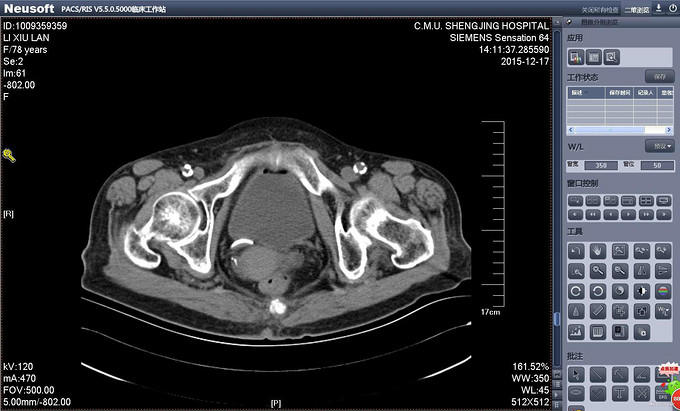

辅助检查:PCNL术后出院前复查CT提示双J管位置位于膀胱内。(图术后复查CT 1、2) 输尿管镜拔管前再次复查CT提示双J管缩回输尿管内(缩回后CT1、2)